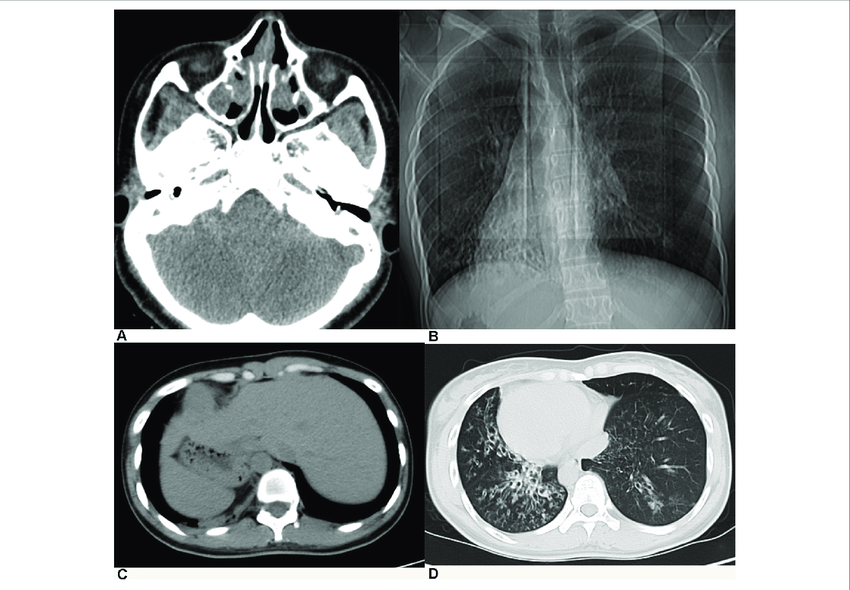

Triad of Kartagener's Syndrome

Kartagener's syndrome is an autosomal recessive genetic disorder. It is characterized by the triad of: 1. situs inversus 2. bronchiectasis 3. chronic sinusitis Reference: https://www.ncbi.nlm.nih.gov/pmc/articles/PMC3519024/ Image via: https://www.researchgate.net/publication/335322558_Identification_of_Pathogenic_Mutations_and_Investigation_of_the_NOTCH_Pathway_Activation_in_Kartagener_Syndrome/figures?lo=1